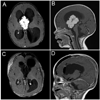

Figures